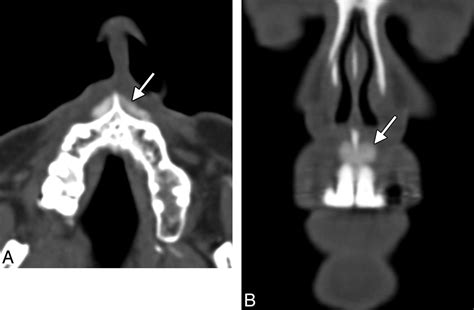

In diagnostic imaging, the Anterior Nasal Spine is a valuable landmark for interpreting radiographs and CT scans. Its consistent position and density make it easily identifiable on imaging studies, aiding in the diagnosis and treatment planning of various conditions. For example, in cases of nasal trauma, the Anterior Nasal Spine can help in assessing the extent of the injury and planning the appropriate surgical intervention.

Additionally, the Anterior Nasal Spine is used as a reference point in cephalometric analysis, a technique used in orthodontics to assess the skeletal and dental relationships of the craniofacial complex. This analysis helps in planning orthodontic treatments and predicting treatment outcomes.